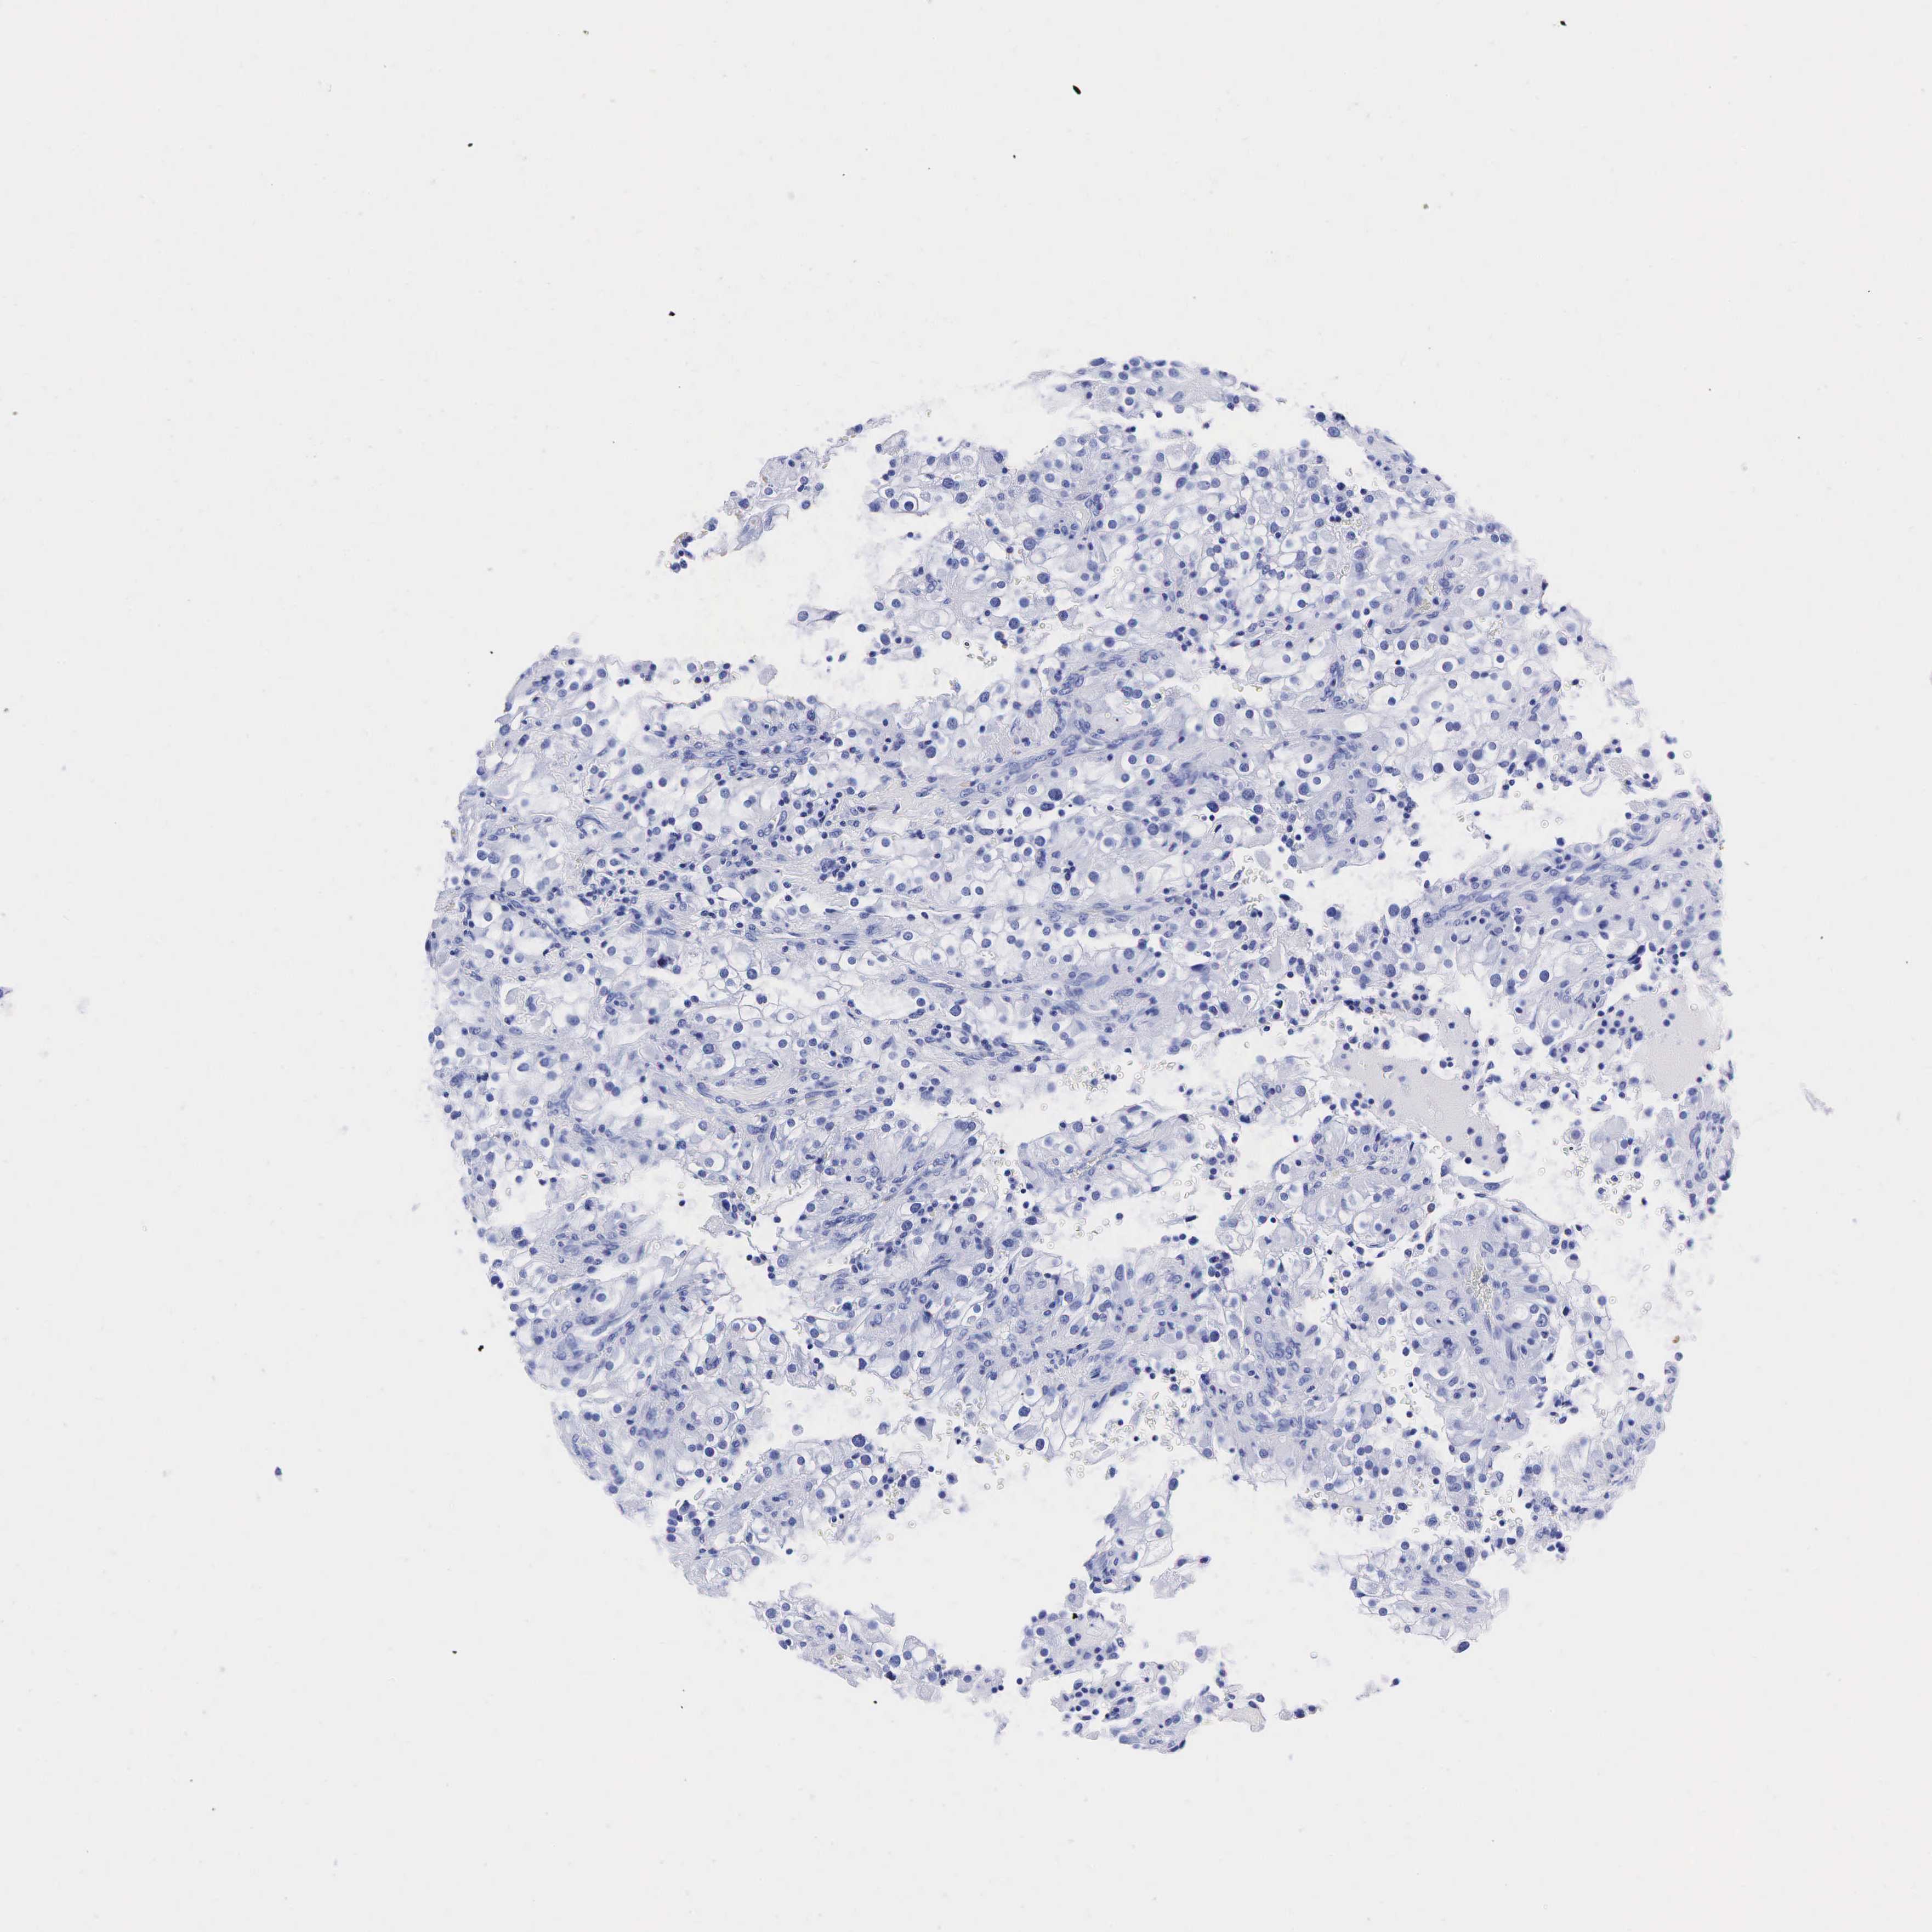

KIDNEY RENAL CLEAR CELL CARCINOMA (VALIDATION) - Interactive survival scatter ploti

The Survival Scatter plot shows the clinical status (i.e. dead or alive) for all individuals in the patient cohort, based on the same data that underlies the corresponding Kaplan-Meier plots. Patients that are alive at last time for follow-up are shown in blue and patients who have died during the study are shown in red.

The x-axis shows the expression levels (FPKM) of the investigated gene in the tumor tissue at the time of diagnosis. The y-axis shows the follow-up time after diagnosis (years). Both axes are complimented with kernel density curves demonstrating the data density over the axes. The top density plot shows the expression levels (FPKM) distribution among dead (red) and alive patients (blue). The right density plot shows the data density of the survived years of dead patients with high and low expression levels respectively, stratified using the cutoff indicated by the vertical dashed line through the Survival Scatter plot. This cutoff is automatically defined based on the FPKM cutoff that minimizes the p-score. The cutoff can be changed by dragging the vertical line or by entering a cutoff value in the square labeled "Current cut-off".

Under the Survival Scatter plot the p-score landscape (black curve; left axis) is shown together with dead median separation (red curve; right axis). Dead median separation is the difference in median mRNA expression between patients who have died with high and low expression, respectively. It is calculated as follows: median FPKM expression of dead patients with high expression - median FPKM expression of dead patients with low expression. This is intended to aid the user in visually exploring custom cutoffs and the associated p-scores and dead median separation.

Individual patient data is displayed and can be filtered by clicking on one or more of the category buttons on the top of the page. Categories describing expression level and patient information include: high, low, alive, dead, female, male and tumor stages. The scale of the x-axis can be toggled between linear and log-scale by clicking on the "x log" button. Mouse-over function shows TCGA ID, patient information and mRNA expression (FPKM) for each patient.

& Survival analysisi

Kaplan-Meier plots summarize results from analysis of correlation between mRNA expression level and patient survival. Patients were divided based on level of expression into one of the two groups "low" (under cut off) or "high" (over cut off). X-axis shows time for survival (years) and y-axis shows the probability of survival, where 1.0 corresponds to 100 percent.

TG is not prognostic in Kidney Renal Clear Cell Carcinoma (validation)

Best expression cut offi

Based on the FPKM value of each gene, patients were classified into two groups and association between prognosis (survival) and gene expression (FPKM) was examined. The best expression cut-off refers the FPKM value that yields maximal difference with regard to survival between the two groups at the lowest log-rank P-value. Best expression cut-off was selected based on survival analysis .

When clicking on this number, the vertical dashed line indicating cut-off, the interactive survival plot, and the Kaplan-Meier curve will be adjusted to show results based on the best expression cut-off.

: 1.36

TCGA RNA samplesi

RNA-seq data is reported as average FPKM (number Fragments Per Kilobase of exon per Million reads), generated by the The Cancer Genome Atlas (TCGA) .

Normal distribution across the dataset is visualized with box plots, shown as median and 25th and 75th percentiles. Points are displayed as outliers if they are above or below 1.5 times the interquartile range. FPKM values of the individual samples are presented next to the box plot.

Average pTPM 1.0

Number of samples 100